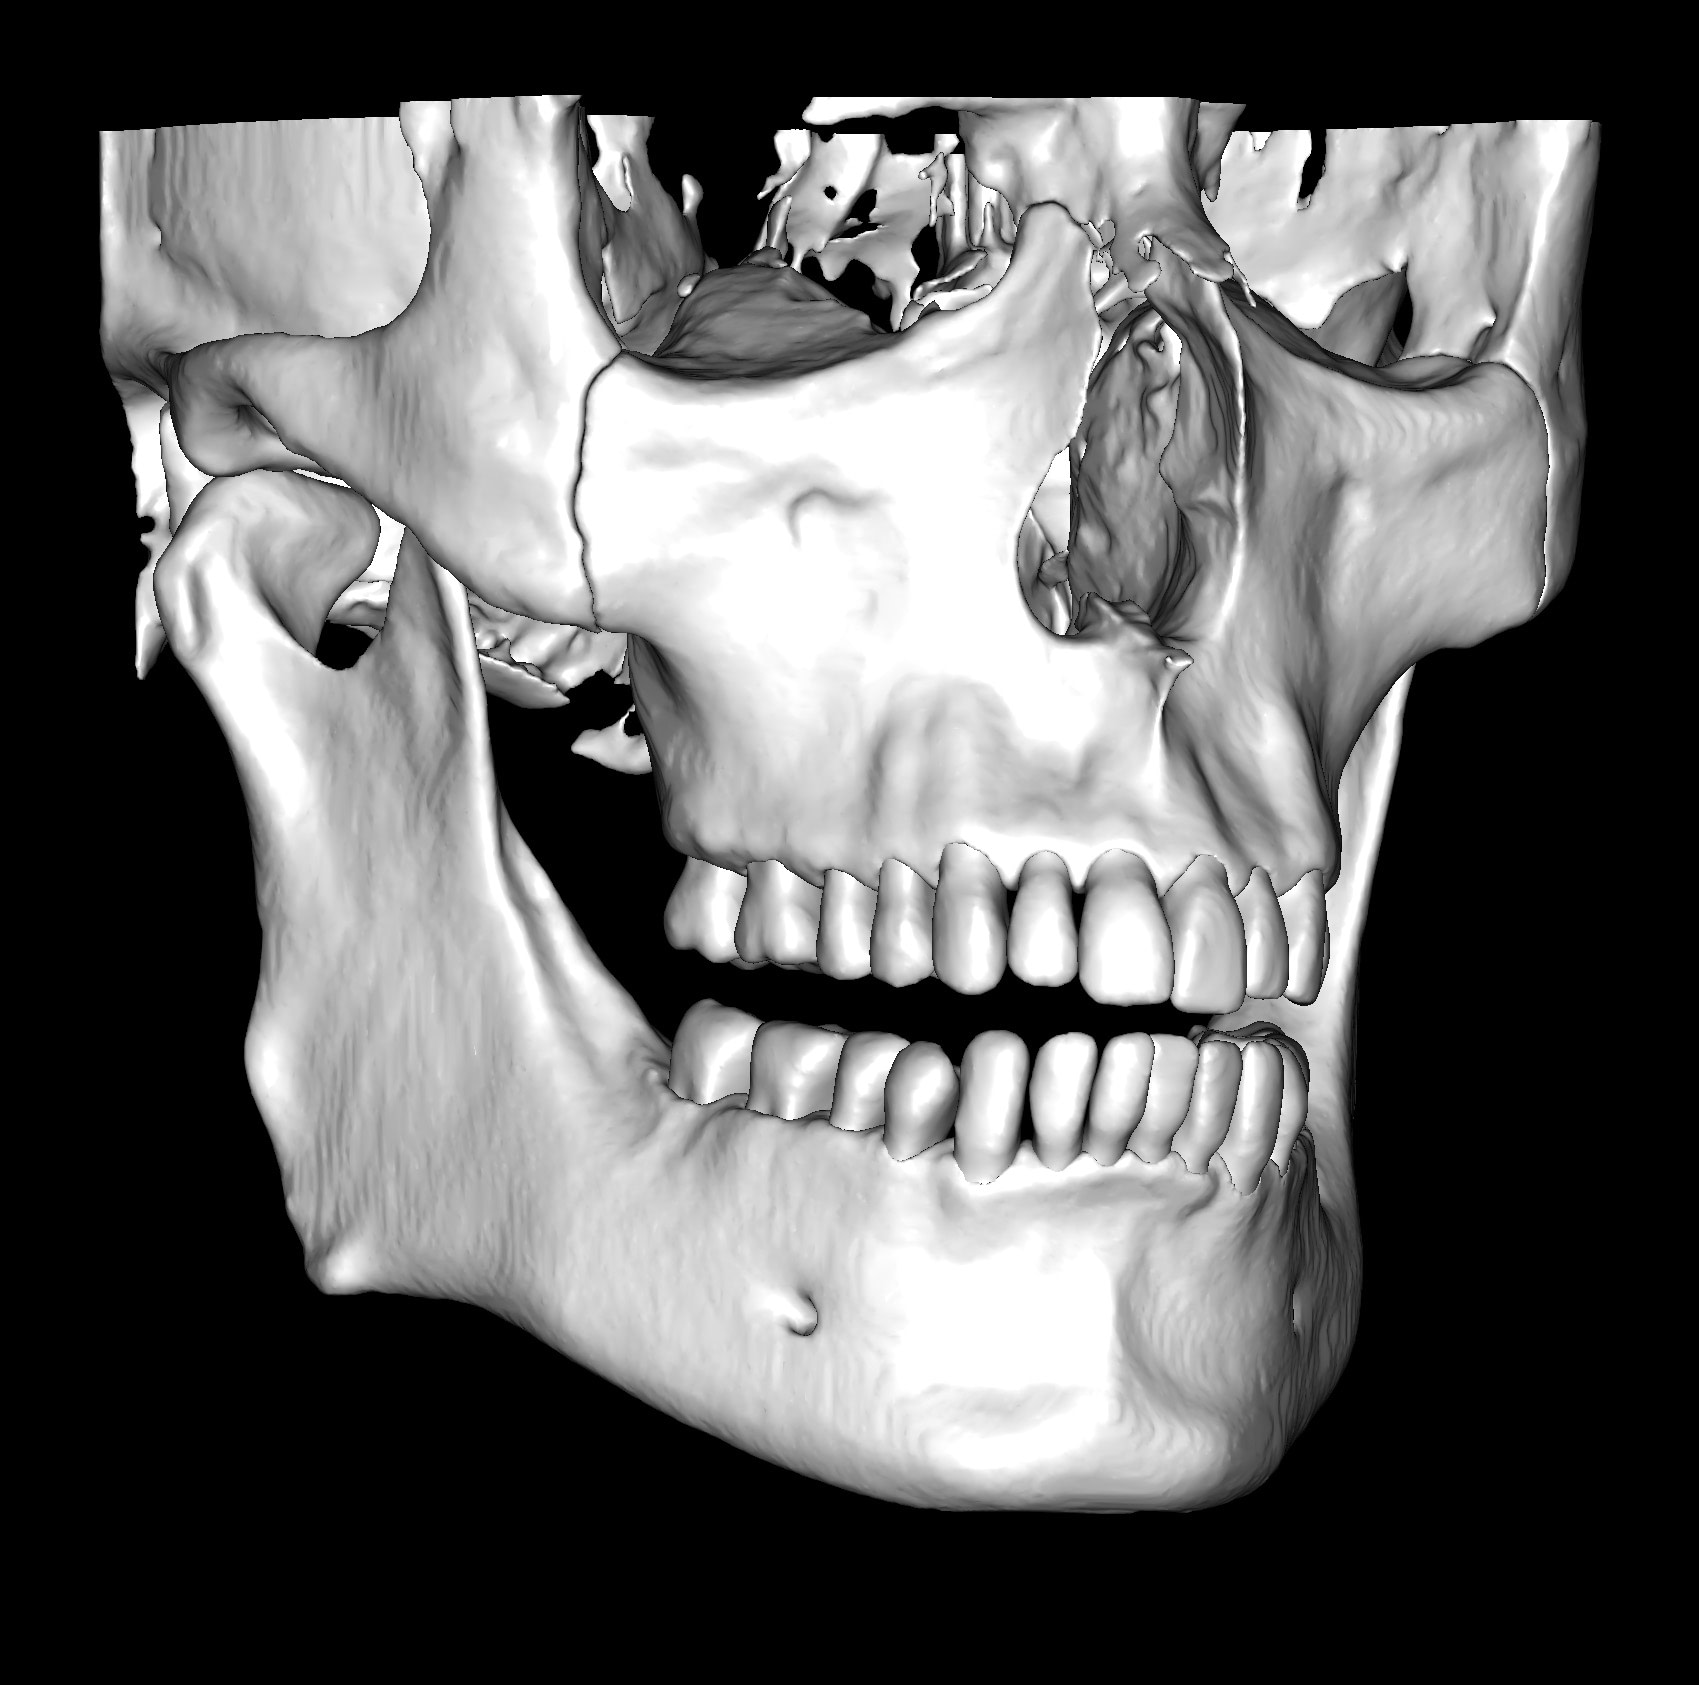

This is one feature that actually made Diagnocat very popular early on. It was the only software that made CBCT segmentation easy. Nowadays, there are several different companies and software that carry out segmentation. Diagnocat was the first and is still arguably the best at it.

So what is Segmentation? It basically means taking the CBCT and delineating all the different 3D structures, bones, individual teeth, etc.

These can then be individually exported via the software by generating STL files from CBCT dicom data. This can be used in other dental software. Jaw STLs can be used in Modjaw (jaw motion capture) for TMJ analysis, for example. As well as in exocad to help visualize the jaws for surgical planning or guide creation.

Being able to take a DICOM file and turn it into STLs is useful for a host of different CAD/CAM indications.

CBCT Segmentation into STL

Generate STL files from CBCT DICOM data.

Generate maxilla and mandible in one STL file or face, teeth, maxilla, mandible, airway, cranial base, canals as separate STL files.